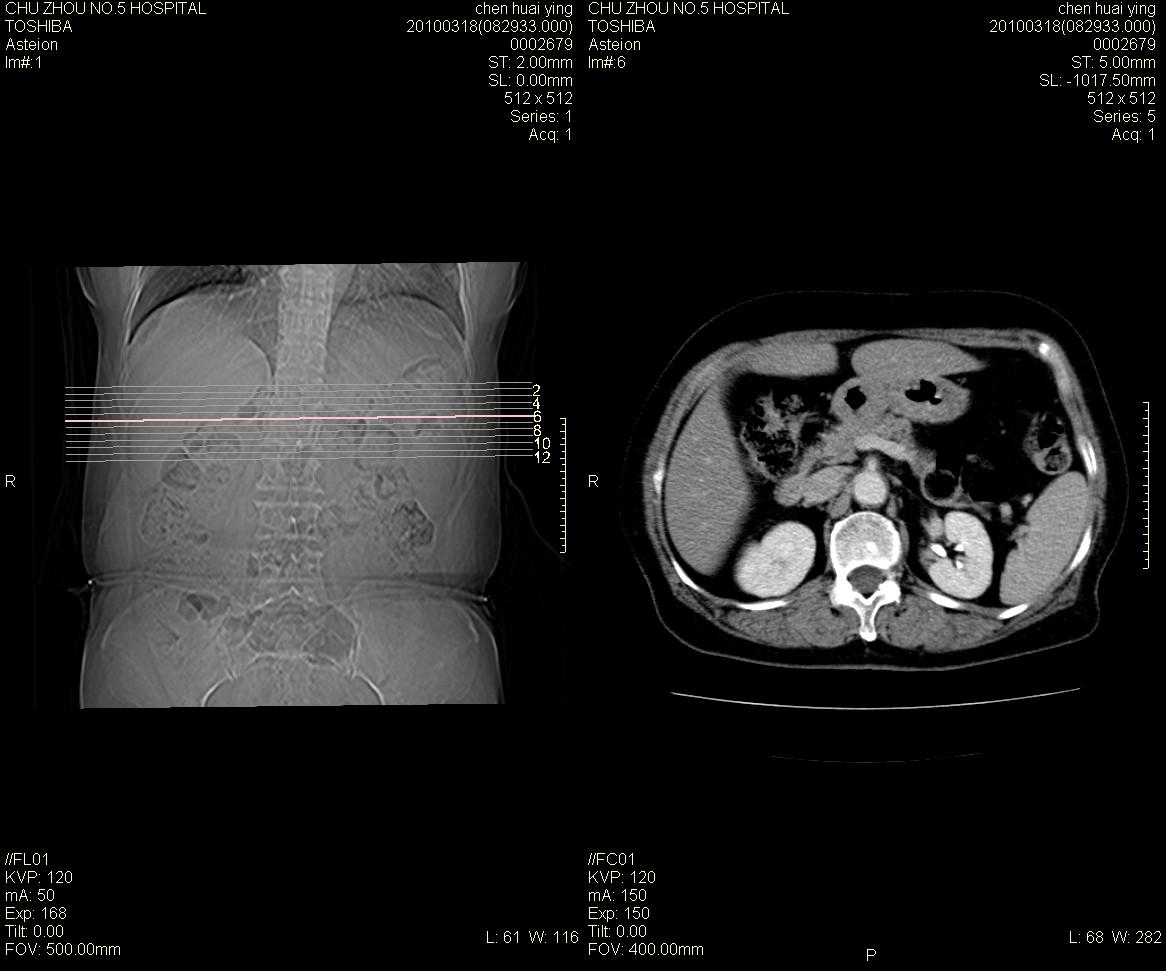

标题: CT25148 肾上腺增强

ct25148增强图片

动脉期太早了,扫的有点低。考虑良性占位右侧肾上腺嗜铬细胞瘤并坏死囊变可能性大,神经鞘瘤不排除。

右侧肾上腺占位性病变,病人是否有高血压?嗜铬细胞瘤?

右侧肾上腺嗜铬细胞瘤并坏死囊变可能性大

考虑双侧肾上腺肿瘤性病变。